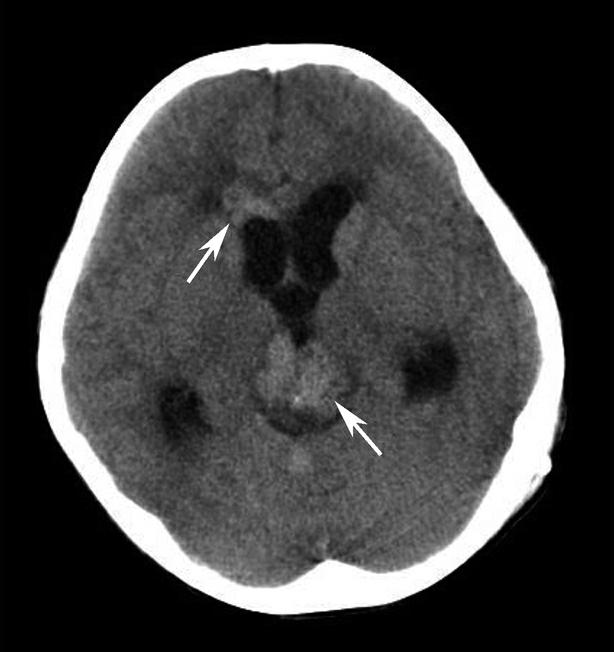

Alberta卒中项目早期CT评分(Alberta stroke program early CT score,ASPECTS)是一种评价急性缺血性卒中患者大脑中动脉供血区早期缺血性改变的简单、可靠、系统化的方法,是常用的脑卒中评定量表之一,可对缺血性病变快速进行半定量评价,有助于判定溶栓效果和远期预后。该评分主要基于CT平扫,具体分区如下(图1-2-76)所示,即选取大脑中动脉供血区2个层面。分区后共10个区域,每个区域记1分。评分时任何区域只要有低密度灶,则扣除该区域得分。正常脑ASPECTS评分为满分(10分),若MCA供血区广泛梗死累及全部区域时,则ASPECTS评分为0分。

图1-2-76 ASPECTS评分脑组织分区

A.在基底节层面(即丘脑和纹状体平面),分为各级分支M 1 、M 2 、M 3 、岛叶(缩写I)、豆状核(缩写L)、尾状核(缩写C)和内囊(缩写IC)后肢等7个区域;B.在基底节以上层面(基底节层面上2cm),包括M 4 、M 5 和M 6 。